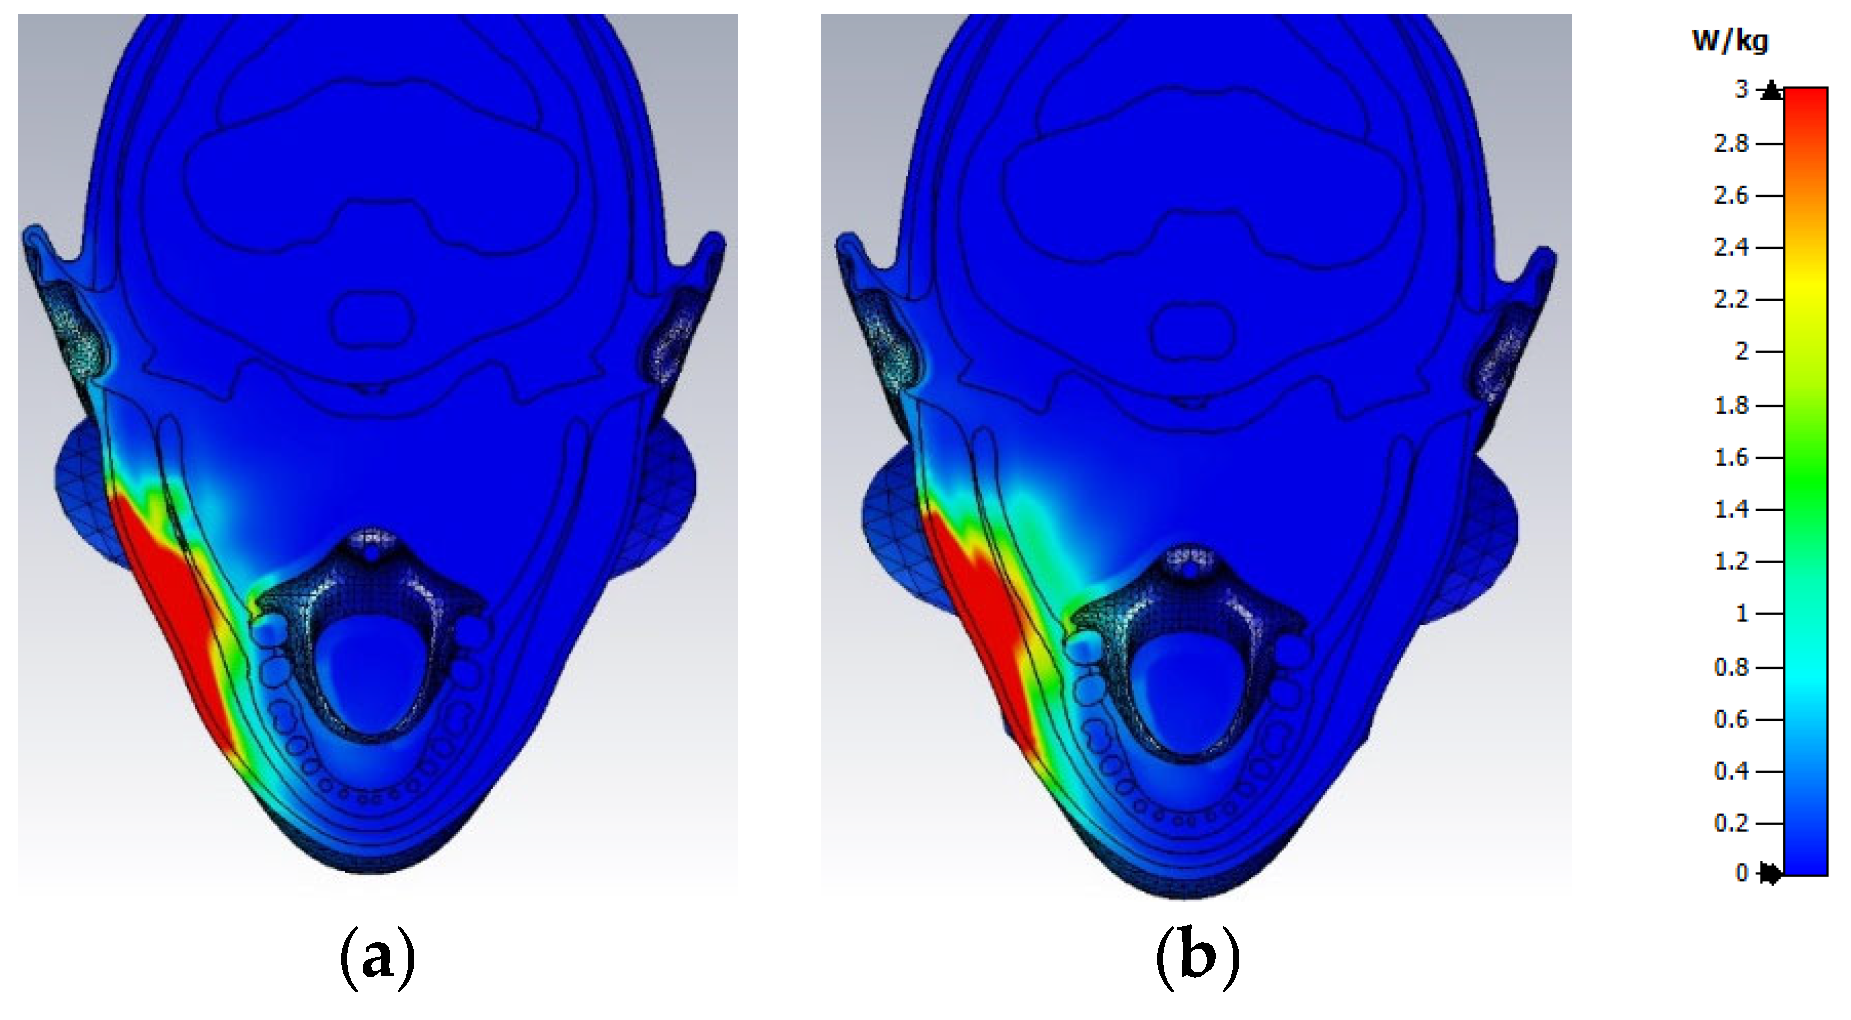

3.2. Distribution of SAR Values Within the Model of the Head of a User